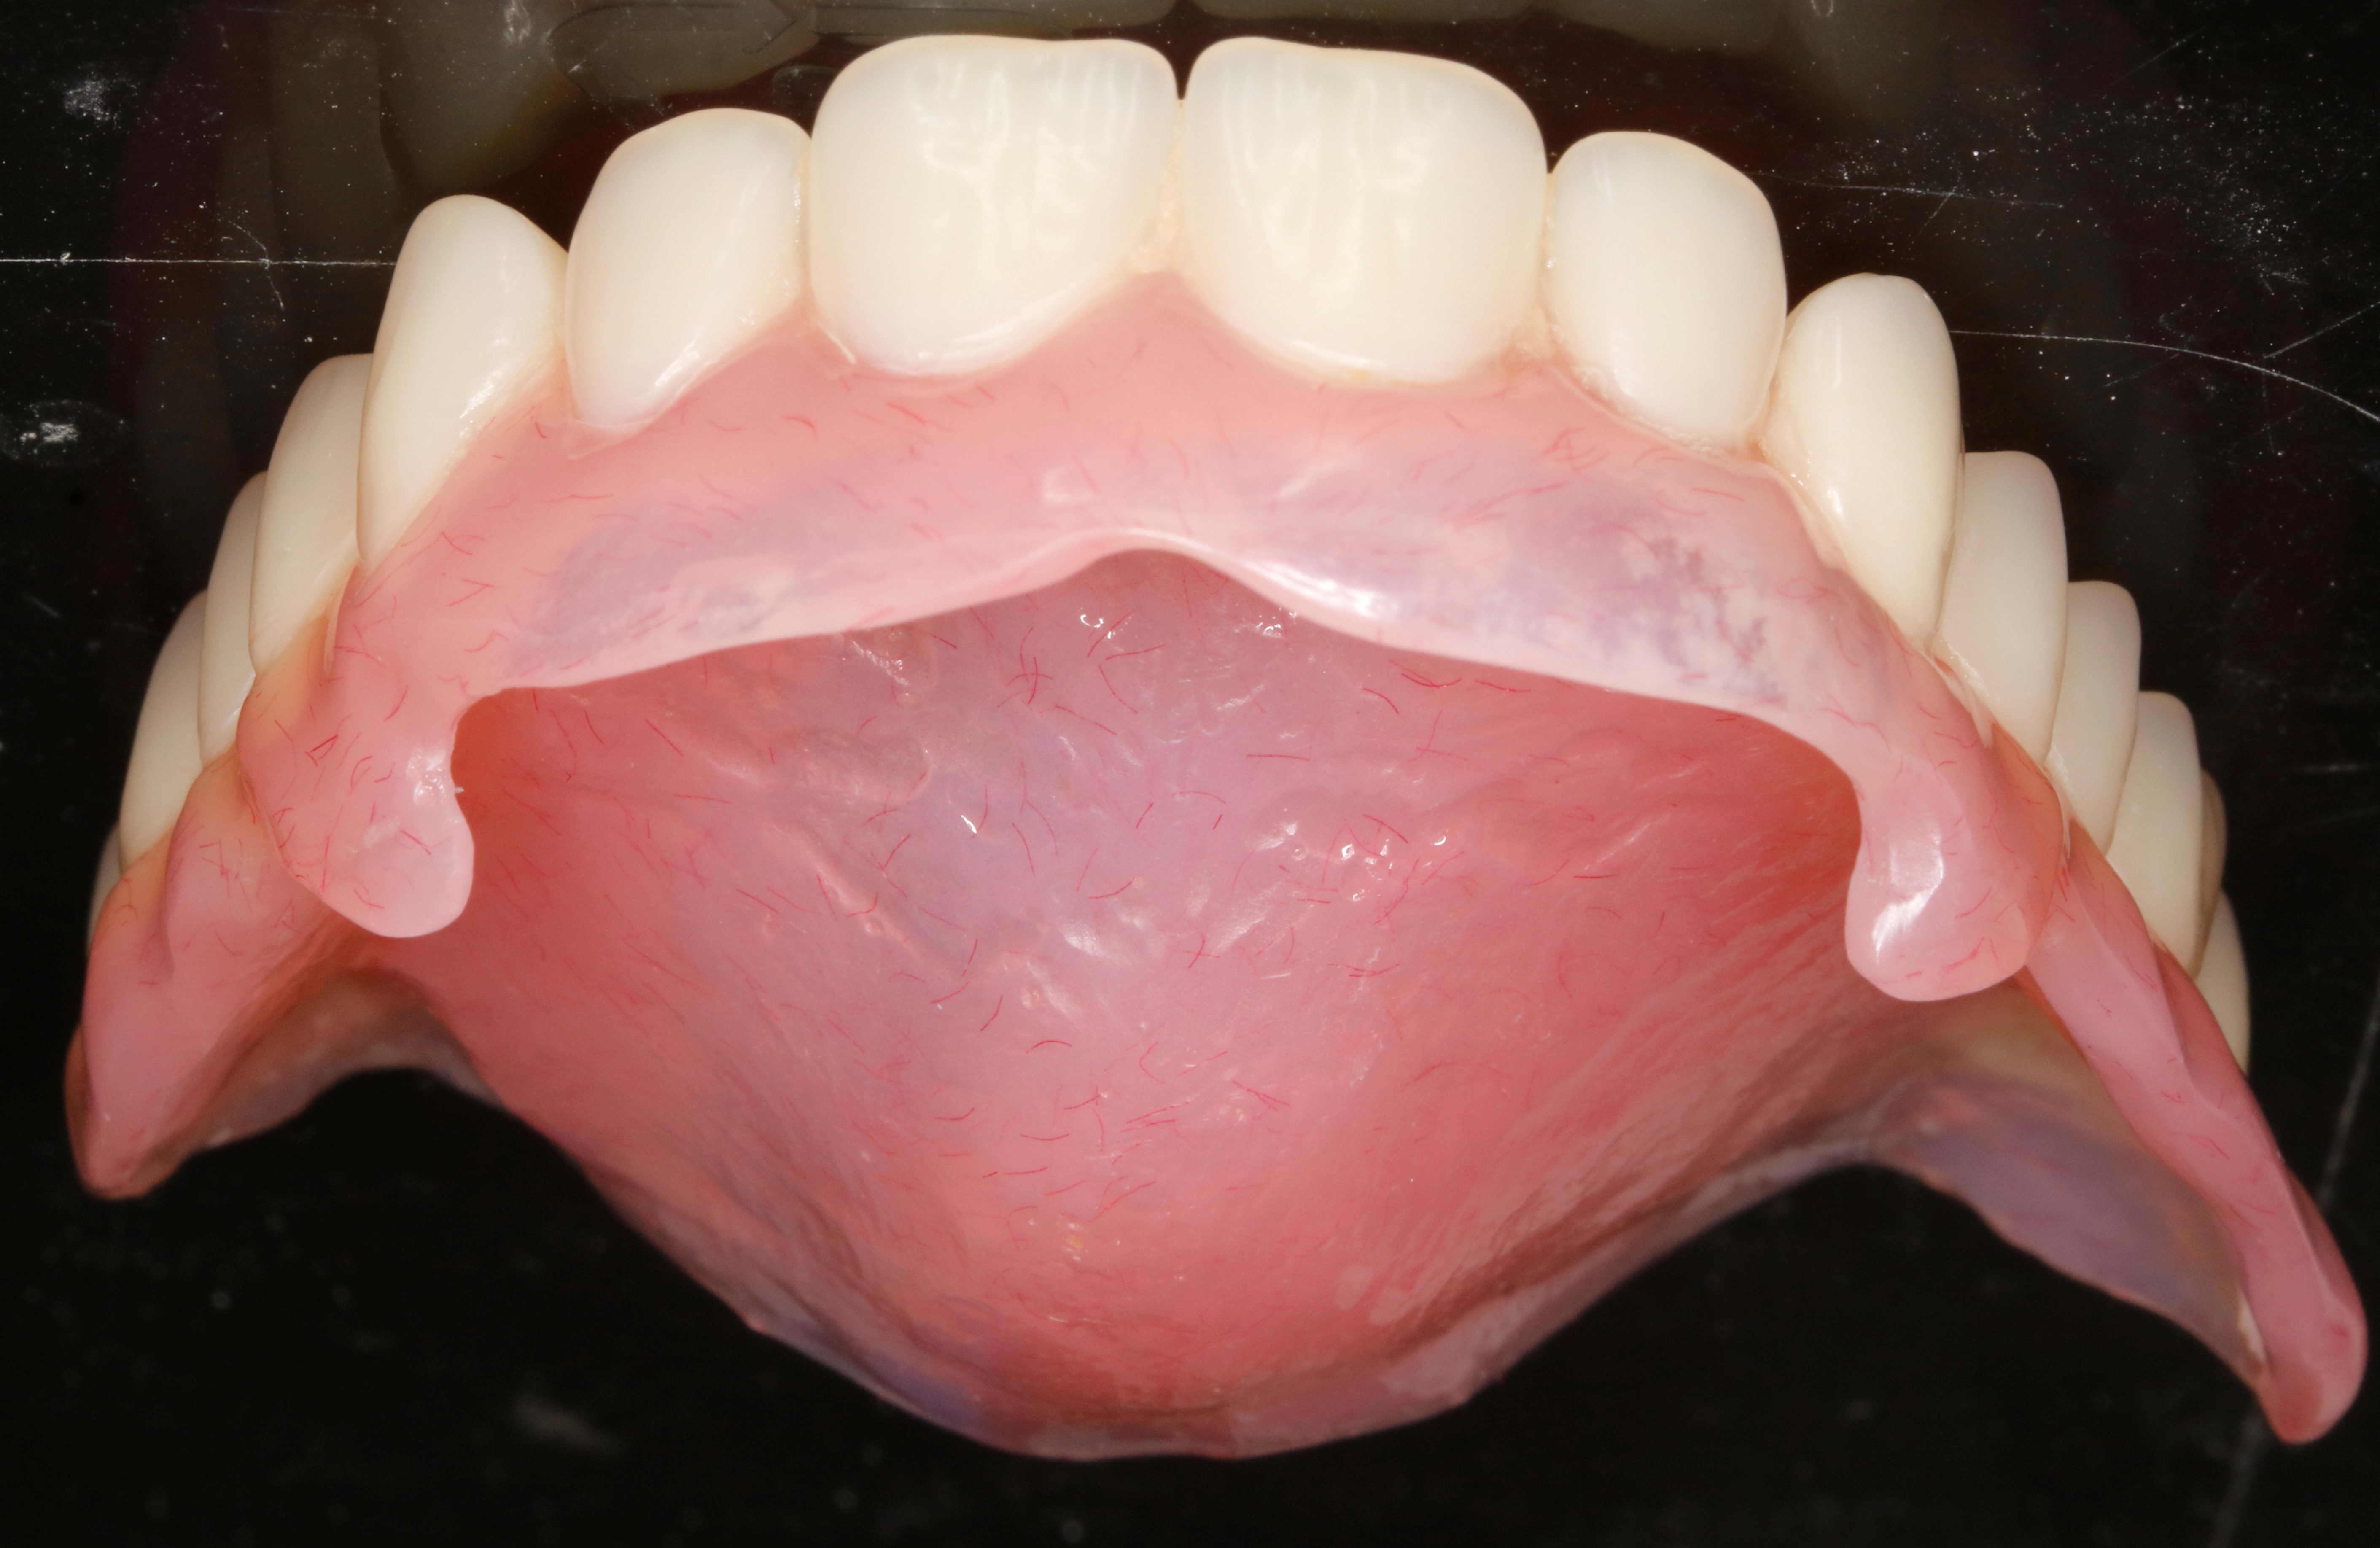

ça ç est mon complet raie-Manta avec ses 2 crochets à os .

Jolie empreinte mon ami!-)

En fait c est un complet immediat suite a des extractions du bloc ant .

Et tu sais comme ils sont ces sto , ils te laissent des bosses de partout .

Du coup tout l os de devant est en contre depouille . D ou les crochets a os .